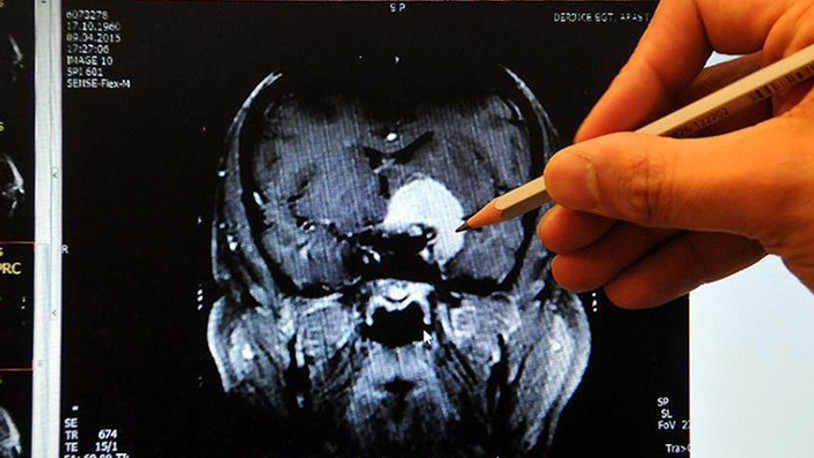

Türk profesör koronavirüsün beyne etkisini yazdı: Küçültüyor

Prof. Dr. Osman Müftüoğlu, koronavirüsün beyin dokusunda harabiyetine ciddi bir boyut getiren yeni bir araştırmayı yazdı.

Prof. Dr. Osman Müftüoğlu, bugün Hürriyet’te “COVID-19 beyni küçültüyor” başlıklı bir yazı kaleme aldı. Uzmanların koronavirüsün insan üzerindeki etkisiyle ilgili değerlendirmelerini ve yapılan araştırmaları köşesinde inceleyen Prof. Müftüoğlu, “Koronavirüs’ün beyin dokusunda da harabiyetlere yol açabileceği, bunun kısa vadeli sonuçlarından birinin de adına ister ‘post viral sendrom’, ister ‘COVID-19 ile ilişkili beyin sisi’ diyelim, ciddi neticelerinin olabileceğini zaten biliyorduk, biliyoruz. Ne var ki yeni bir araştırma, sürece başka ve ciddi bir boyut daha getirdi: Beyin küçülmesi” dedi.

COVID-19 sonrasında gelişen beyin/bellek sorunlarını daha iyi anlayabilmemizi ve açıklayabilmemizi sağlayabileceğini düşündüğüm yeni ve önemli bir çalışmanın ön bilgileri geçtiğimiz günlerde yayımlandı. Araştırma İngiltere kaynaklı. Araştırmada İngiliz yurttaşların sağlık bilgilerinin depolandığı biyolojik veri bankasından (UK BIOBANK) yararlanılmış. Araştırmacılar önce 45 bin kişinin COVID-19 salgınından önce kaydedilmiş beyin görüntülerini incelemişler. Sonra da bunların içinden COVID-19 teşhisi konulanları yeniden çağırıp beyinlerinde ne gibi değişiklikler olduğunu anlamak için beyin taramalarından geçirmişler. Araştırmanın özet sonucu oldukça şaşırtıcı. Beynin “gri cevher” olarak bilinen ve bilgileri işleyen nöronlardan oluşan ana dokusunda Koronavirüs'le enfekte olanlar ve olmayanlar arasında önemli ve belirgin farklılıklar saptamışlar.

Bu değişimlerin de daha ziyade ön (prontal) ve yan (temporal) loblarda olduğunu gözlemlemişler. COVID-19 geçiren grupta özellikle beynin bu bölümlerinde gri cevherin kalınlığının azaldığını, doku kaybının fazlaca olduğunu fark etmişler. Peki, bu kayıp ne anlama geliyor? Böyle bir kaybın uzun vadede ne gibi sonuçları olabilir?

Yaşımız ilerledikçe beynimizdeki gri maddenin hacmi giderek azalıyor. Bu azalma beynimizin özellikle bellek ile ilgili fonksiyonlarında bir ölçüde gerilemeye yol açıyor. Bu araştırmada COVID-19’dan etkilendiği belirtilen beyin bölgeleri arasında “hipokampus” da var. Biliyoruz ki hipokampus bellek ve bilişsel süreçler için beynimizin son derece önemli bir bölgesi. Araştırmada saptanan bu değişimlerin, daha doğrusu beyindeki küçülmenin ileride hafıza gücümüzü etkileyip etkilemeyeceği konusu, ne kadar süreceği ve yeniden normale dönüp dönmeyeceği meselesi önümüzdeki günlerin önemli tartışma alanlarından biri olacak gibi görünüyor.